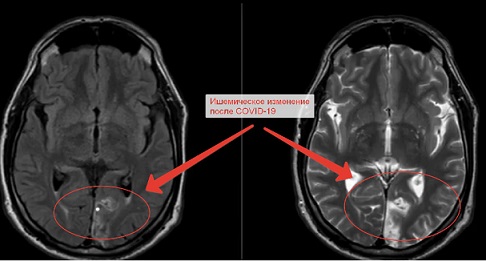

После болезни Covid-19 у жителя Рязани падает зрение. МРТ головного мозга показало причину

Из-за коронавируса у жителя Рязани упало зрение на один глаз. После МРТ мозга узнали, что произошло Мужчина, который проживает в Рязани, обратился в сеть диагностических медцентров «Клиника-Сити». У него начались проблемы со зрением в правом глазу. Рентгенологи одной из клиники сети сделали обследование МРТ в Рязани. Во время процедуры выяснилось, что имеются кистозно-атрофические и глиозные изменения с размерами 4,2*3 и 2*5,3 сантиметров. Локализацией служила левая затылочная часть. Врачи-эксперты медцентра «Клиника-Сити» предположили, что данная проблема могла быть спровоцирована ранее перенесенным ишемическим инсультом или инфарктом в голове, так как именно в этой части головного мозга находится «зрительная зона». В результате изучения глазных орбит и нервов никаких патологий не было обнаружено. Значит дело было в мозге. В ходе дискуссии с пациентом он рассказал врачам, что летом тяжело переболел COVID-19. Болезнь протекала крайне неудачно для него. Как многим известно, коронавирусная инфекция часто воздействует на сосуды, а также приводит к образованию тромбов в организме. Врачами было установлено после расшифровки снимков томографии, что именно коронавирус вызвал данную проблему. А после проведения диагностики МРТ головного мозга, информация была подтверждена. Сегодня магнитно-резонансная томография занимает первое место в диагностической медицине. Проведение обследований на аппарат 1,5 Тесла еще называет «золотым стандартом» в диагностике. Эта процедура наиболее высокоточная и информативная, а также абсолютно безвредна для организма. Чаще всего людям, которые перенесли инсульт назначают именно МРТ. Врачи сети «Клиника-Сити» рекомендуют следить за своим здоровьем. Своевременно обращаться в медицинские центры Рязани за помощью профессионалов. Также сообщаем, что в их центре на Первомайском проспекте, д. 27 проводятся тесты на антитела к COVID-19 и УЗИ сосудов. Вовремя обследуемое заболевание и лечение помогут избежать дальнейших последствий для вашего организма! |